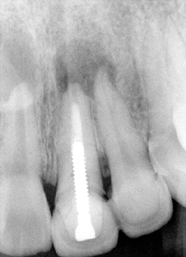

Dental history: #9 fracture at age of 8; #9,10 crowns (joined) 2 years ago; #9 has chronic apical infection, #19 extracted due to caries at age of 15

Remove #9,10 crowns, #9 lingual margin subgingival; pulpal test: #8,10 necrosis. Remove #9 post, redo RCT, #8, 10 RCT, #8,10 in office internal bleaching; #9 cast post, ortho extrusion before #9,10 crowns

#18 mesiolingual tilt, #19 traditional implant and extract #17; once #19 implant is osteointegrated, it is to be used as an anchorage to upright #18, elastics between #15 buccal hook and 18 lingual button to correct linguoversion of #18